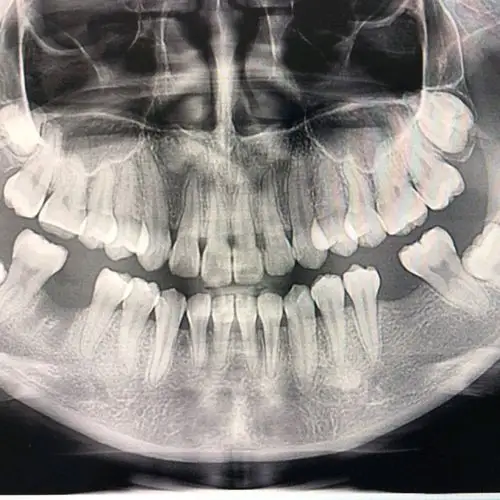

种植牙术前术后拍片对比

吴女士种植带冠后的牙片显示,种植体就位精准,受力均衡